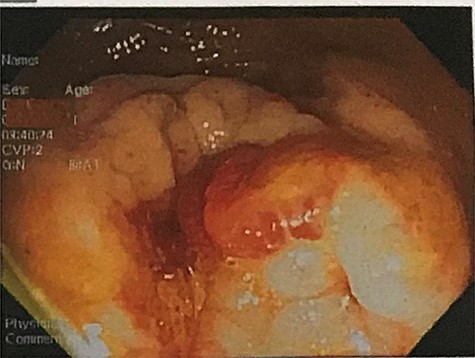

A 32-year-old man with no past medical or surgical history presented to the emergency department (ED) in April 2018, distressed and complaining of worsening pneumaturia for the past 3 days. The patient reported a 2-week history of polyuria, dysuria, suprapubic pain, tenesmus and inability to control his sphincters, prior to the ED-onset presentation. Further history revealed a 50-pound involuntary weight loss in a 5-month period, with partially treated urinary tract infections without resolution. He denied toxic habits, high-risk sexual behavior nor family history for colorectal cancer or inflammatory bowel disease. Based on the symptoms described, the rare triad of Gouverneur’s syndrome related to the EVF was considered. Physical evaluation revealed no palpable anorectal masses, adequate rectal tone and no visible gross blood. Urine analysis showed pyuria, hematuria, proteinuria with urine culture positive for Escherichia coli. Abdominopelvic computed tomography (CT) scan showed circumferential wall thickening of the rectum with surrounding fat stranding and numerous prominent pelvic lymph nodes (Fig. 1). Additionally, the scan showed pericolonic gas and fluid collection with a fistulous tract adjacent to the proximal rectum and the bladder (Fig. 2). In Figure 3, two hepatic hypodense lesions located in the right lobe of the liver were identified suggestive of metastasis. During colonoscopy, at approximately 20 cm from the anal verge a large, firm, irregular, friable, concentric mass was identified obstructing 95% of the lumen (Fig. 4). During surgery, the mass was not amenable for resection, due to its low pelvic location and size; a loop colostomy was performed for decompression, with liver tru-cut needle biopsy. Intraoperative cystoscopy was unsuccessful in placement of ureteral stents due to tumor invasion to the bladder.

Colonoscopy results showing a large, irregular, friable concentric lesion occluding 95% of the lumen, 20 cm from the anal verge.

Pathology report from mass biopsy revealed a moderately differentiated rectal adenocarcinoma, with carcinoembryonic antigen (CEA) (+) and alpha fetoprotein (AFP) (+) levels.